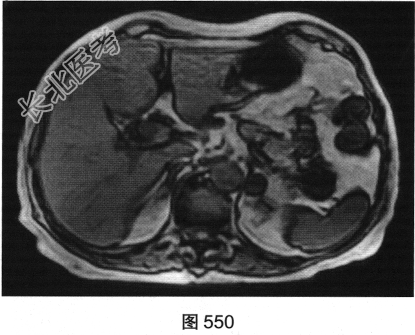

- 多项选择题3.[提示]MRI平扫+增强(图550~图555):T1WI正相位, 左侧肾上腺外侧肢可见类圆形T1WI稍高信号结节。T1WI反相位,结节信号明显减低。T2WI脂肪抑制, 结节呈均匀低信号。动态增强,动脉期结节轻度均匀强化, 静脉期结节呈相对低信号,延迟期结节呈相对低信号。可考虑的鉴别诊断为( )